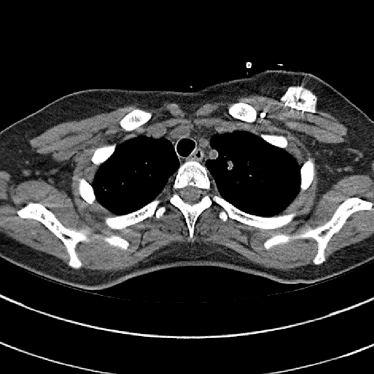

Refer to caption(a) Clinical Standard IRRefer to caption(a) Clinical Standard IR

Refer to caption(b) JENGRefer to caption(b) JENG

Refer to caption(c) Clinical Standard IRRefer to caption(c) Clinical Standard IR

Refer to caption(d) JENGRefer to caption(d) JENG

Figure 14: Qualitative clinical results from a thoracic CT staging dataset for a 12-year-old with osteosarcoma with pulmonary metastases. The clinical standard hybrid IR is shown on the left and JENG is on the right. (a) The clinical standard hybrid IR in lung window with a window center of -600 HU and a window width of 1500 HU. (b) JENG at a resolution comparable to the clinical standard, but with less noise and fewer artifacts. (c) The clinical standard hybrid IR in soft tissue window with a window center of 55 HU and a window width of 440 HU. A metastatic lung cancer nodule can be found in the left upper lobe. (d) JENG in soft tissue window at a comparable resolution, but with less noise and fewer artifacts. Note that JENG is not fully corrected for beam hardening artifacts.

Refer to caption

(a) Clinical Standard Hybrid IR

(b) JENG

Figure 15: An example cross-plane image from the same thoracic dataset as in Fig. 14. (a) A coronal-view image slice of the clinical standard hybrid IR in soft tissue window. (b) JENG at a comparable resolution but with reduced image noise and artifacts.

V.B. Clinical Cases